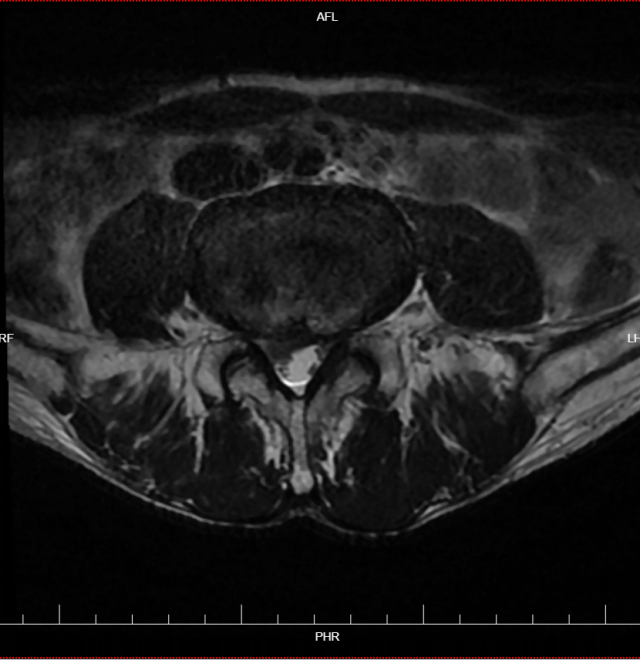

术前检查

腰椎磁共振检查显示,黄先生的腰椎间盘突出明显,神经根受压严重,这正是他症状的根源所在。